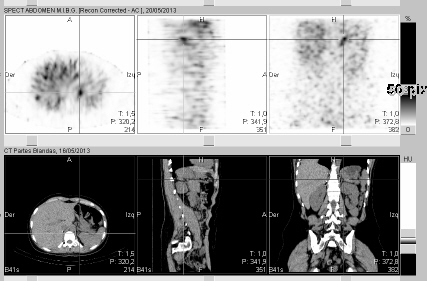

Algunos adenomas atípicos pueden comportarse así, por ello a veces recurrimos a PET y Biopsia.

FEOCROMOCITOMA:

Tumor poco frecuente, secreta catecolaminas, proviene de la médula suprarrenal (ectodermo). Provoca cefalea, ansiedad, palpitaciones fruto del exceso de A y NA. El diagnóstico pasa por la clínica, el laboratorio y la imagen. Son pequeños (2-5 cm) e hipervasculares, pueden tener densidad líquido en su interior y quistes. En RM son hipointensos en T1 y marcadamente hiperintensos en T2. La solución pasa por la extirpación quirúrgica.